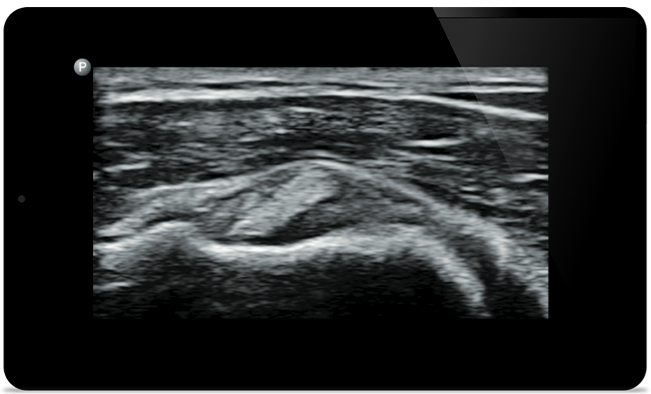

Start treatment with an accurate diagnosis

Lumify helps you see the fine details in muscles, joints, ligaments, tendons and cartilage to make a more accurate diagnosis of injuries.

Lumify can help you assess patients from head to toe, whether it’s plantar fasciitis, tendonitis or bursitis in the patellar tendon, or even shoulder instability in the rotator cuff.

Lumify transducers for MSK

Lumify L12-4 broadband linear array transducer